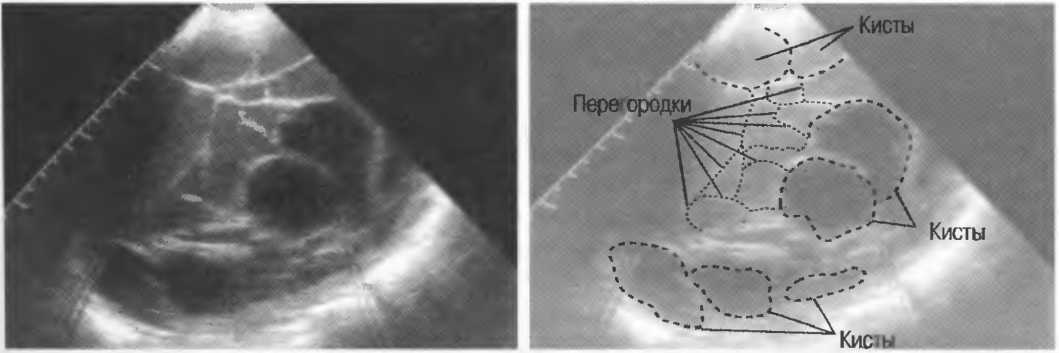

Артефакты могут определяться в любой кистозной структуре (такой, например, как мочевой пузырь или желчный пузырь) и чаще определяются ближе кпереди, становясь менее выраженными на глубине. Они исчезают или меняют свой характер при изменении положения датчика. Но истинные структуры в кисте, такие как перегородки, сохраняют свое местоположение независимо от положения датчика. Истинные отражения имеют место при наличии сгустка крови, гноя, некротической взвеси, и все это чаще визуализируется по задней стенке: если эти структуры не фиксированы к стенке, они изменяют свое положение при перемене положения тела пациента (рис. 16).

Рис. 16а. Злокачественная киста яичника: крупная киста с внутренней перегородкой, которая остается в прежнем положении при сканировании пациентки в различных положениях.

Осадок в кисте может флотировать, формируя уровень, изменяющий свое положение при перемещении пациента (рис. 16б,в).

Рис. 16б. Киста с усилением по задней стенке, латеральными тенями и осадком в полости.

Рис. 16в. Этот же пациент, что и на рис. 16б. Сканирование осуществляется в разных положениях больного. Уровень, создаваемый осадком, смещается.